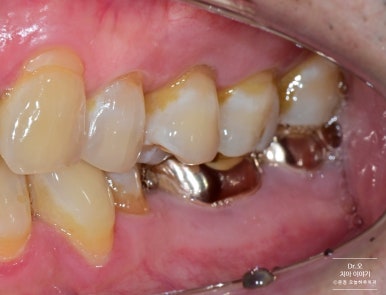

▶ 케이스 2: 기존 레진 탈락 부위 재수복

전 후

- 반대편 부위는 레진이 접착 실패로 탈락한 상태였습니다.

- 탈락된 부위는 치태가 쉽게 끼고 충치 위험이 증가하기 때문에

다시 수복을 진행했습니다.